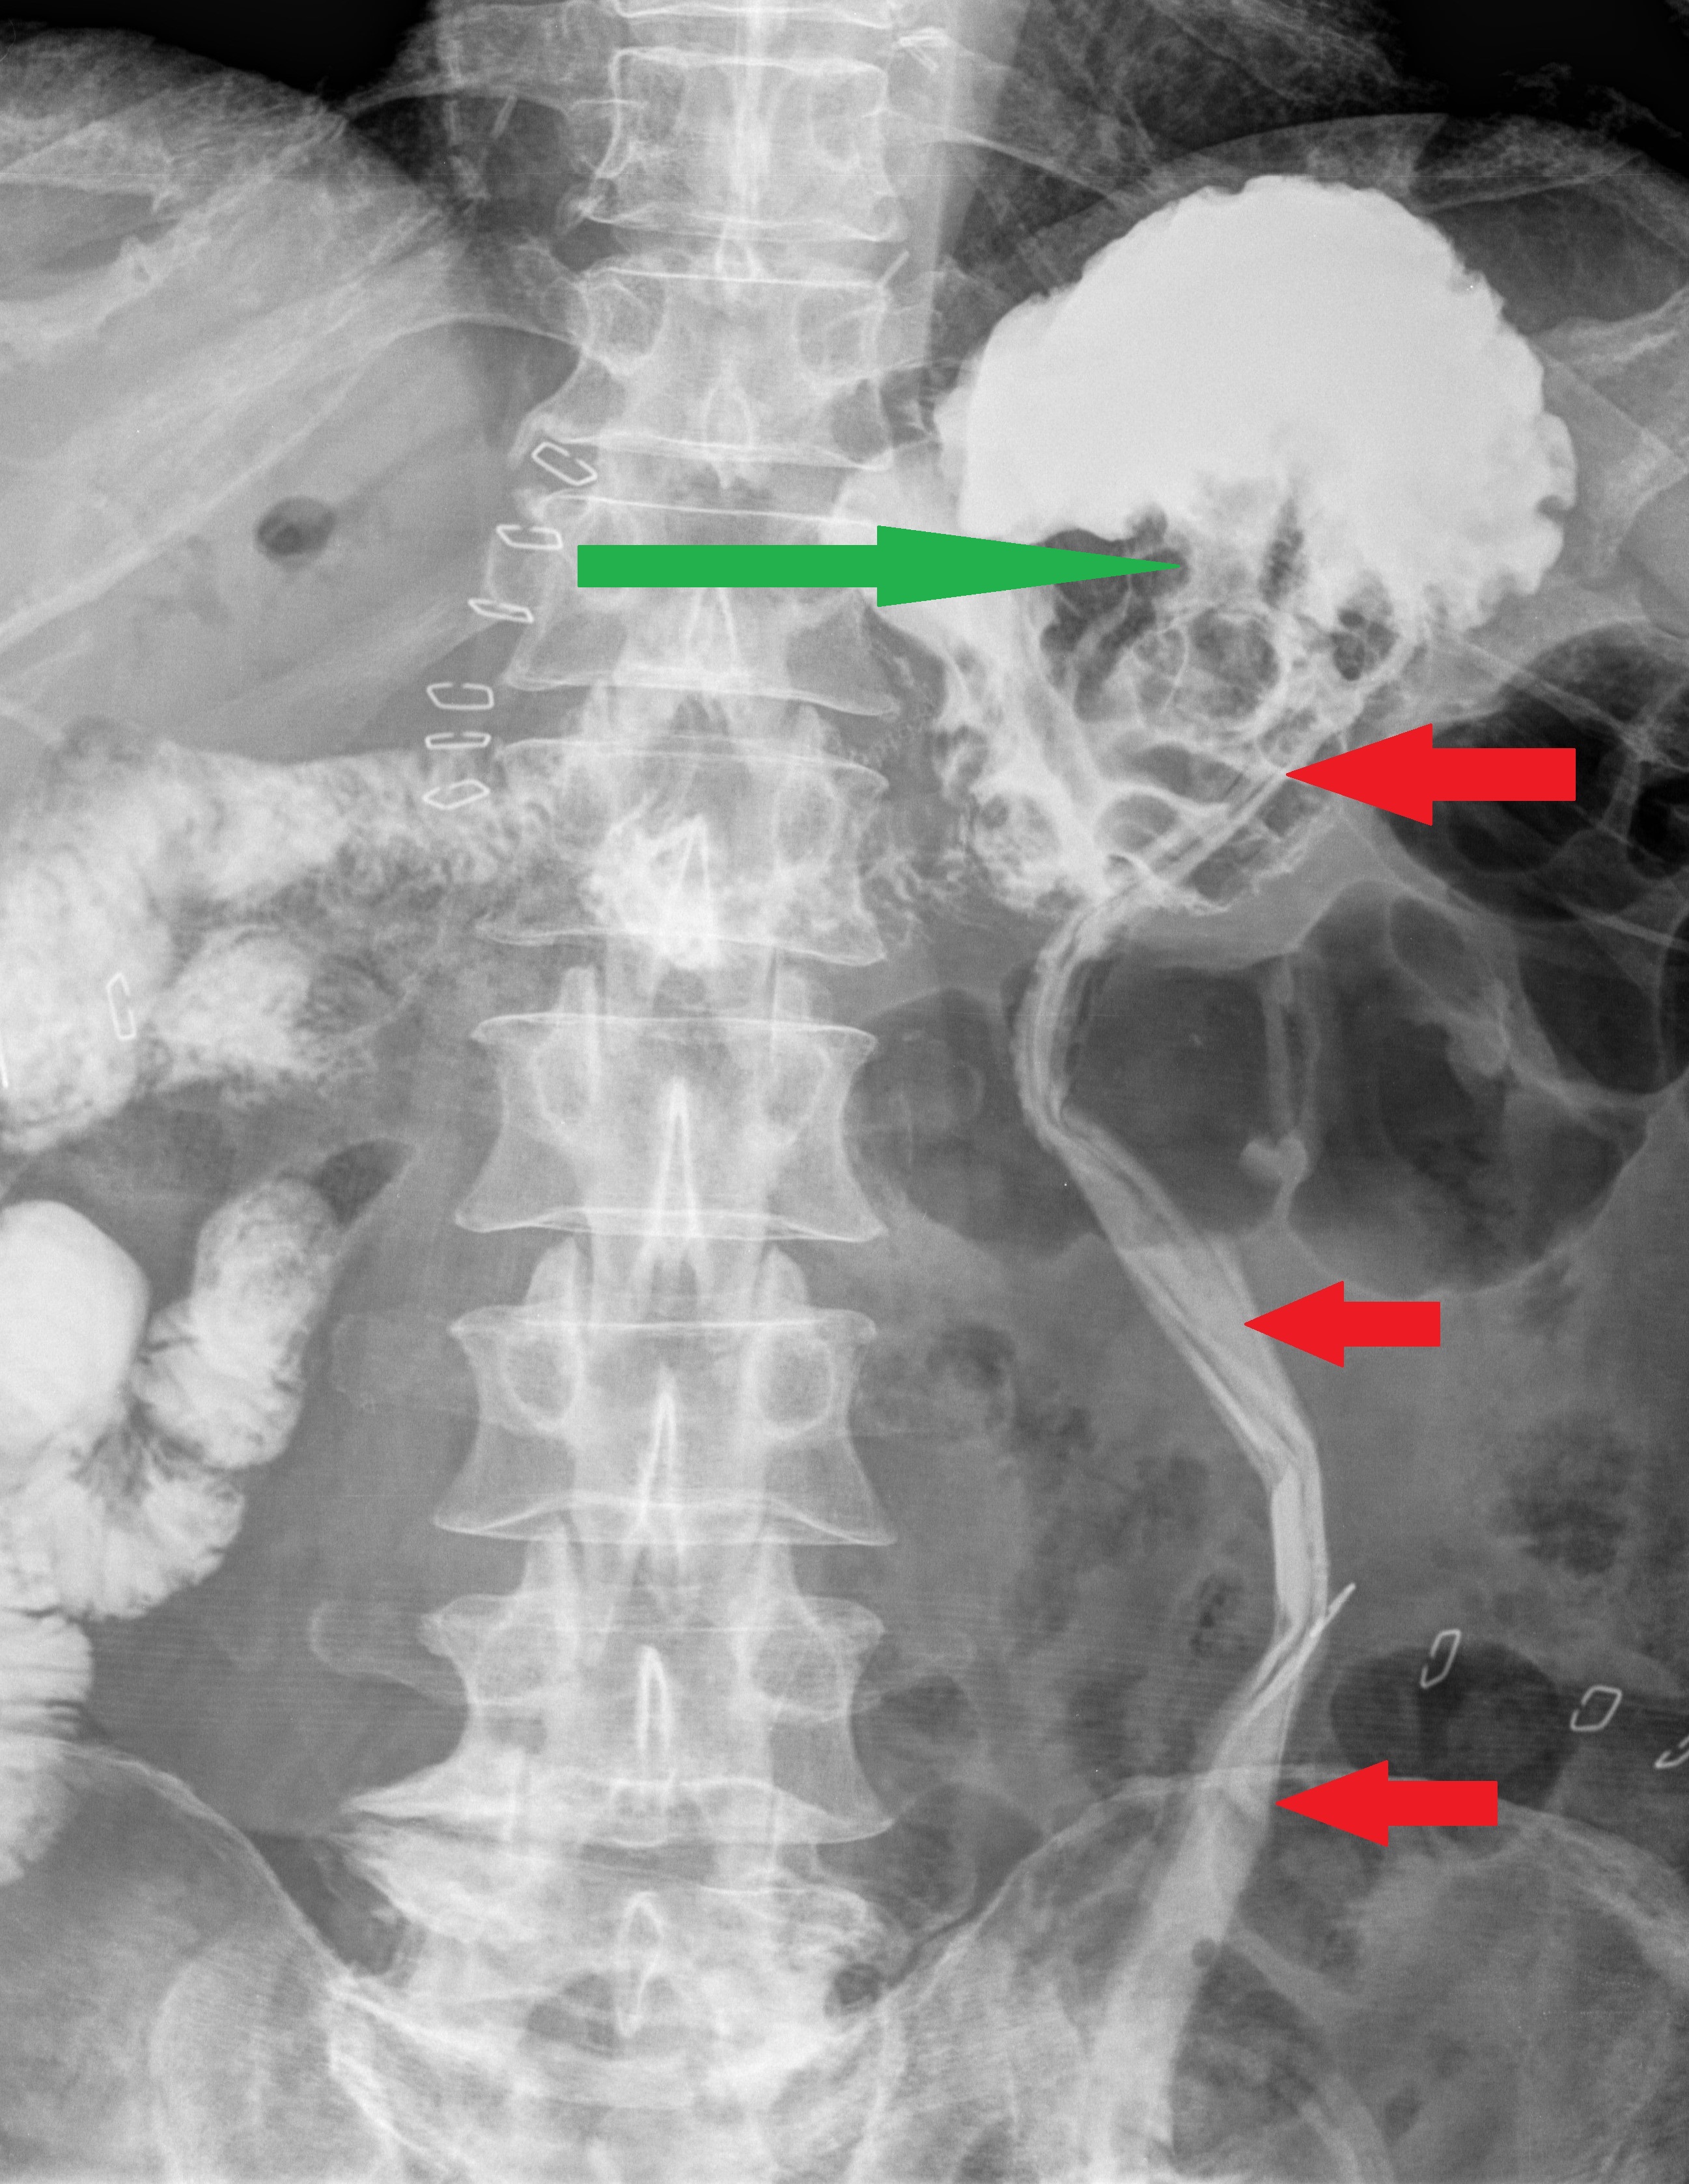

Gastrografin swallow pass . The intragastric site of the drainage tube is evident . The protruding mass in the stomach ( green arrow ) represents the pancreatic remnant pancreato-gastric anastomosis (Courtesy Dr. V. Penopoulos)